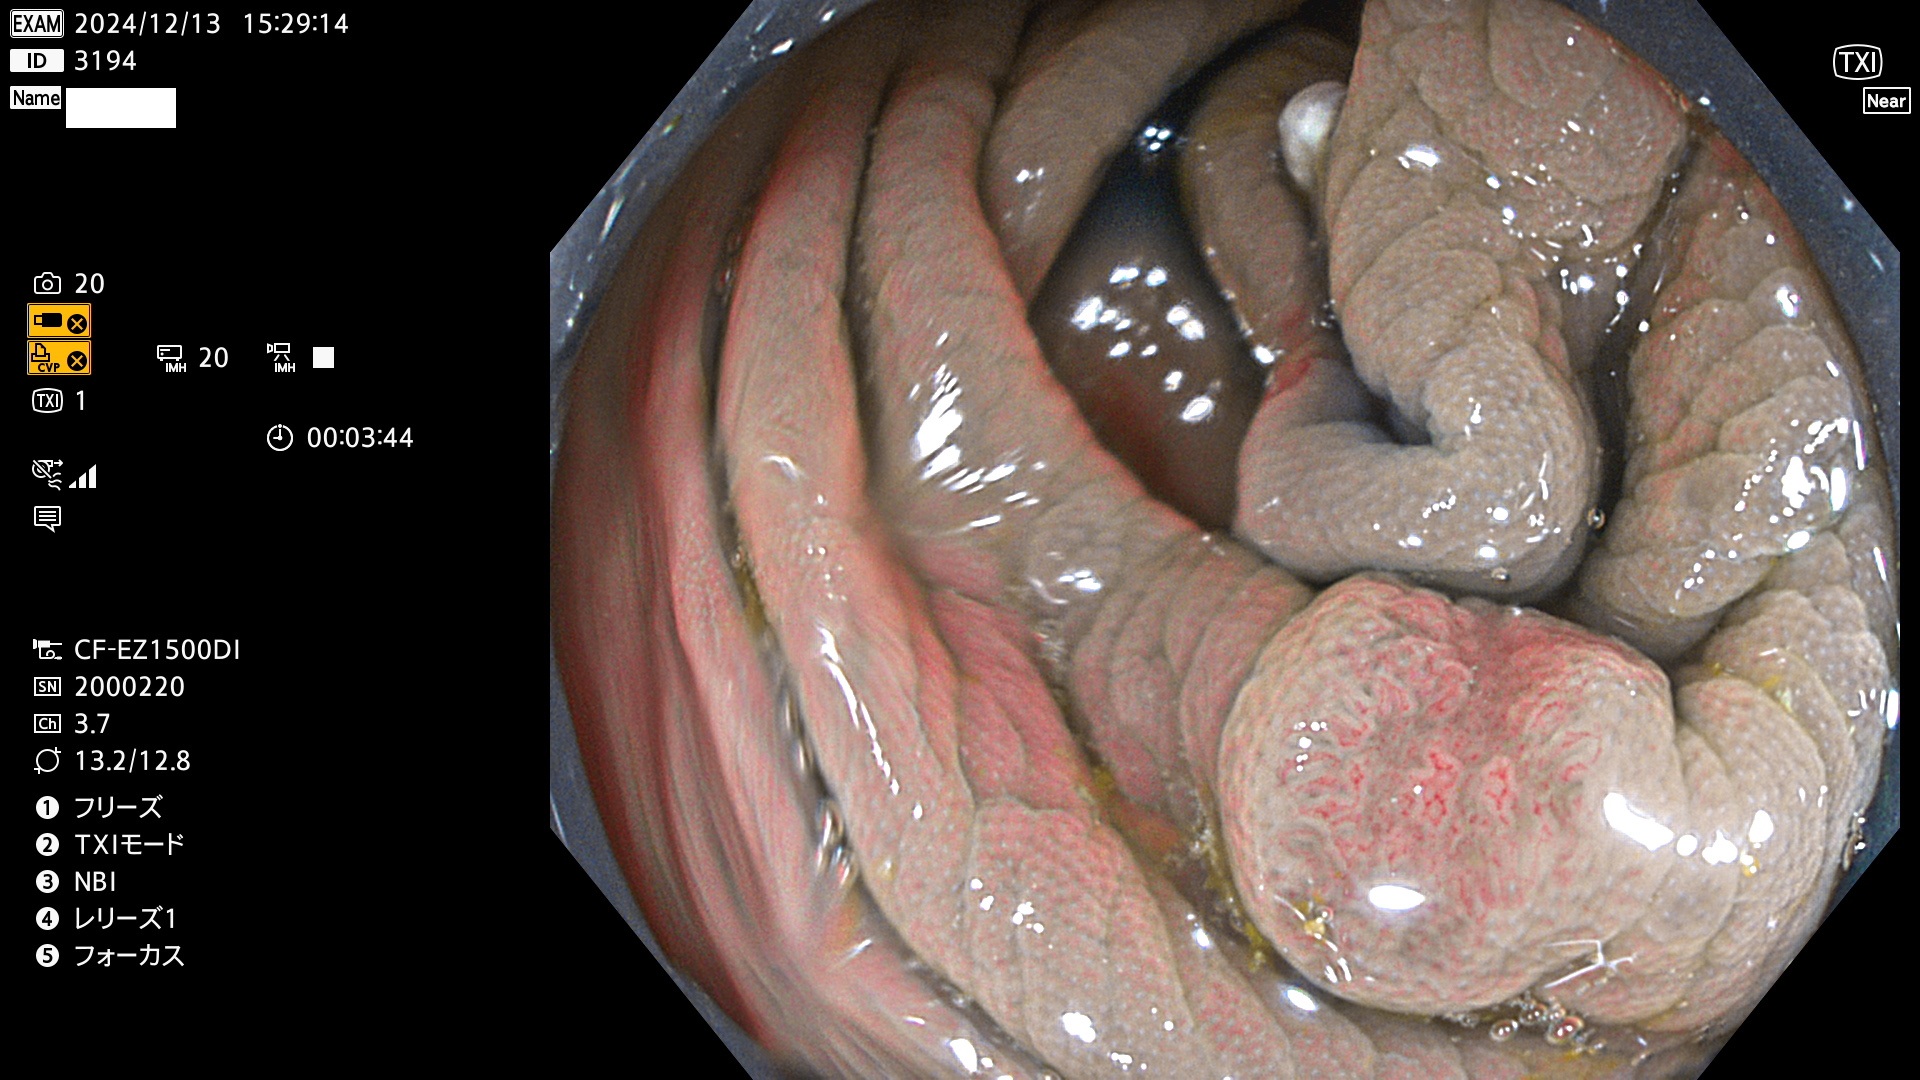

完全に平坦な物をUb、陥凹している物をUcと呼びます。最も発見が難しく危険な病変です。

専門的)Uc=De Novo癌? 内視鏡の解像度が低かった時代、このような説もありました。しかし今日の高精度内視鏡では良性の微小なUc型腺腫が日常的に見つかります。私見ですが「Ucこそが多段階発癌(Adenoma-Carcinoma Sequence)のMain Route」と考えます。

毎週の検査(木・金・土・日)に発見されたUb、Uc型・腺腫を、その週の日曜の夜にUPし1週間、提示します。

抽出の対象期間 2024年12月12日〜12月16日の5日間(60件の検査)13件 (13/60=21%)